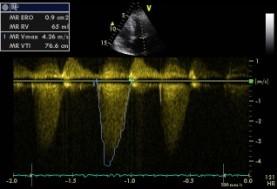

Echokardiografie: LEVÁ KOMORA bez dilatace a hypertrofie, s normální systolickou funkcí a regionální kinetikou kromě D shape, EF LK 55-60%. Diastolická funkce: porucha relaxace LK. PRAVÁ KOMORA FAC PK 18%, TAPSE 13 mm, Vt 9 cm/s, dilatace a hypertrofie PK, těžká prekapilární PH, odhadovaný PASP 90 mmHg, MPAP 55 mmHg, malý perikardiální výpotek

Echokardiografie: LEVÁ KOMORA bez dilatace a hypertrofie, s normální systolickou funkcí a regionální kinetikou kromě D shape, EF LK 55-60%. Diastolická funkce: porucha relaxace LK. PRAVÁ KOMORA FAC PK 19%, TAPSE 17 mm, Vt 9 cm/s, dilatace a hypertrofie PK, těžká prekapilární PH, odhadovaný PASP 130

mmHg, perikardiální výpotek